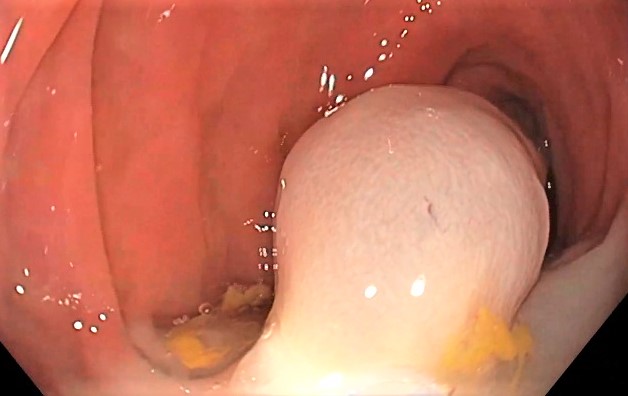

También son comunes los pseudopólipos, crecimientos de tejido inflamatorio resultantes de la regeneración mucosa. Aunque son más frecuentes en la colitis ulcerosa, se pueden ver en pacientes con enfermedad de Crohn.

Durante la colonoscopia, aparecen como protrusiones irregulares y a menudo múltiples, que sobresalen de la mucosa colónica inflamada.

Las Guías de Práctica Clínica recomiendan que durante la colonoscopia se realicen biopsias dirigidas de pseudopólipos representativos o sospechosos, pero no es necesario extirpar ni muestrear todas las lesiones.